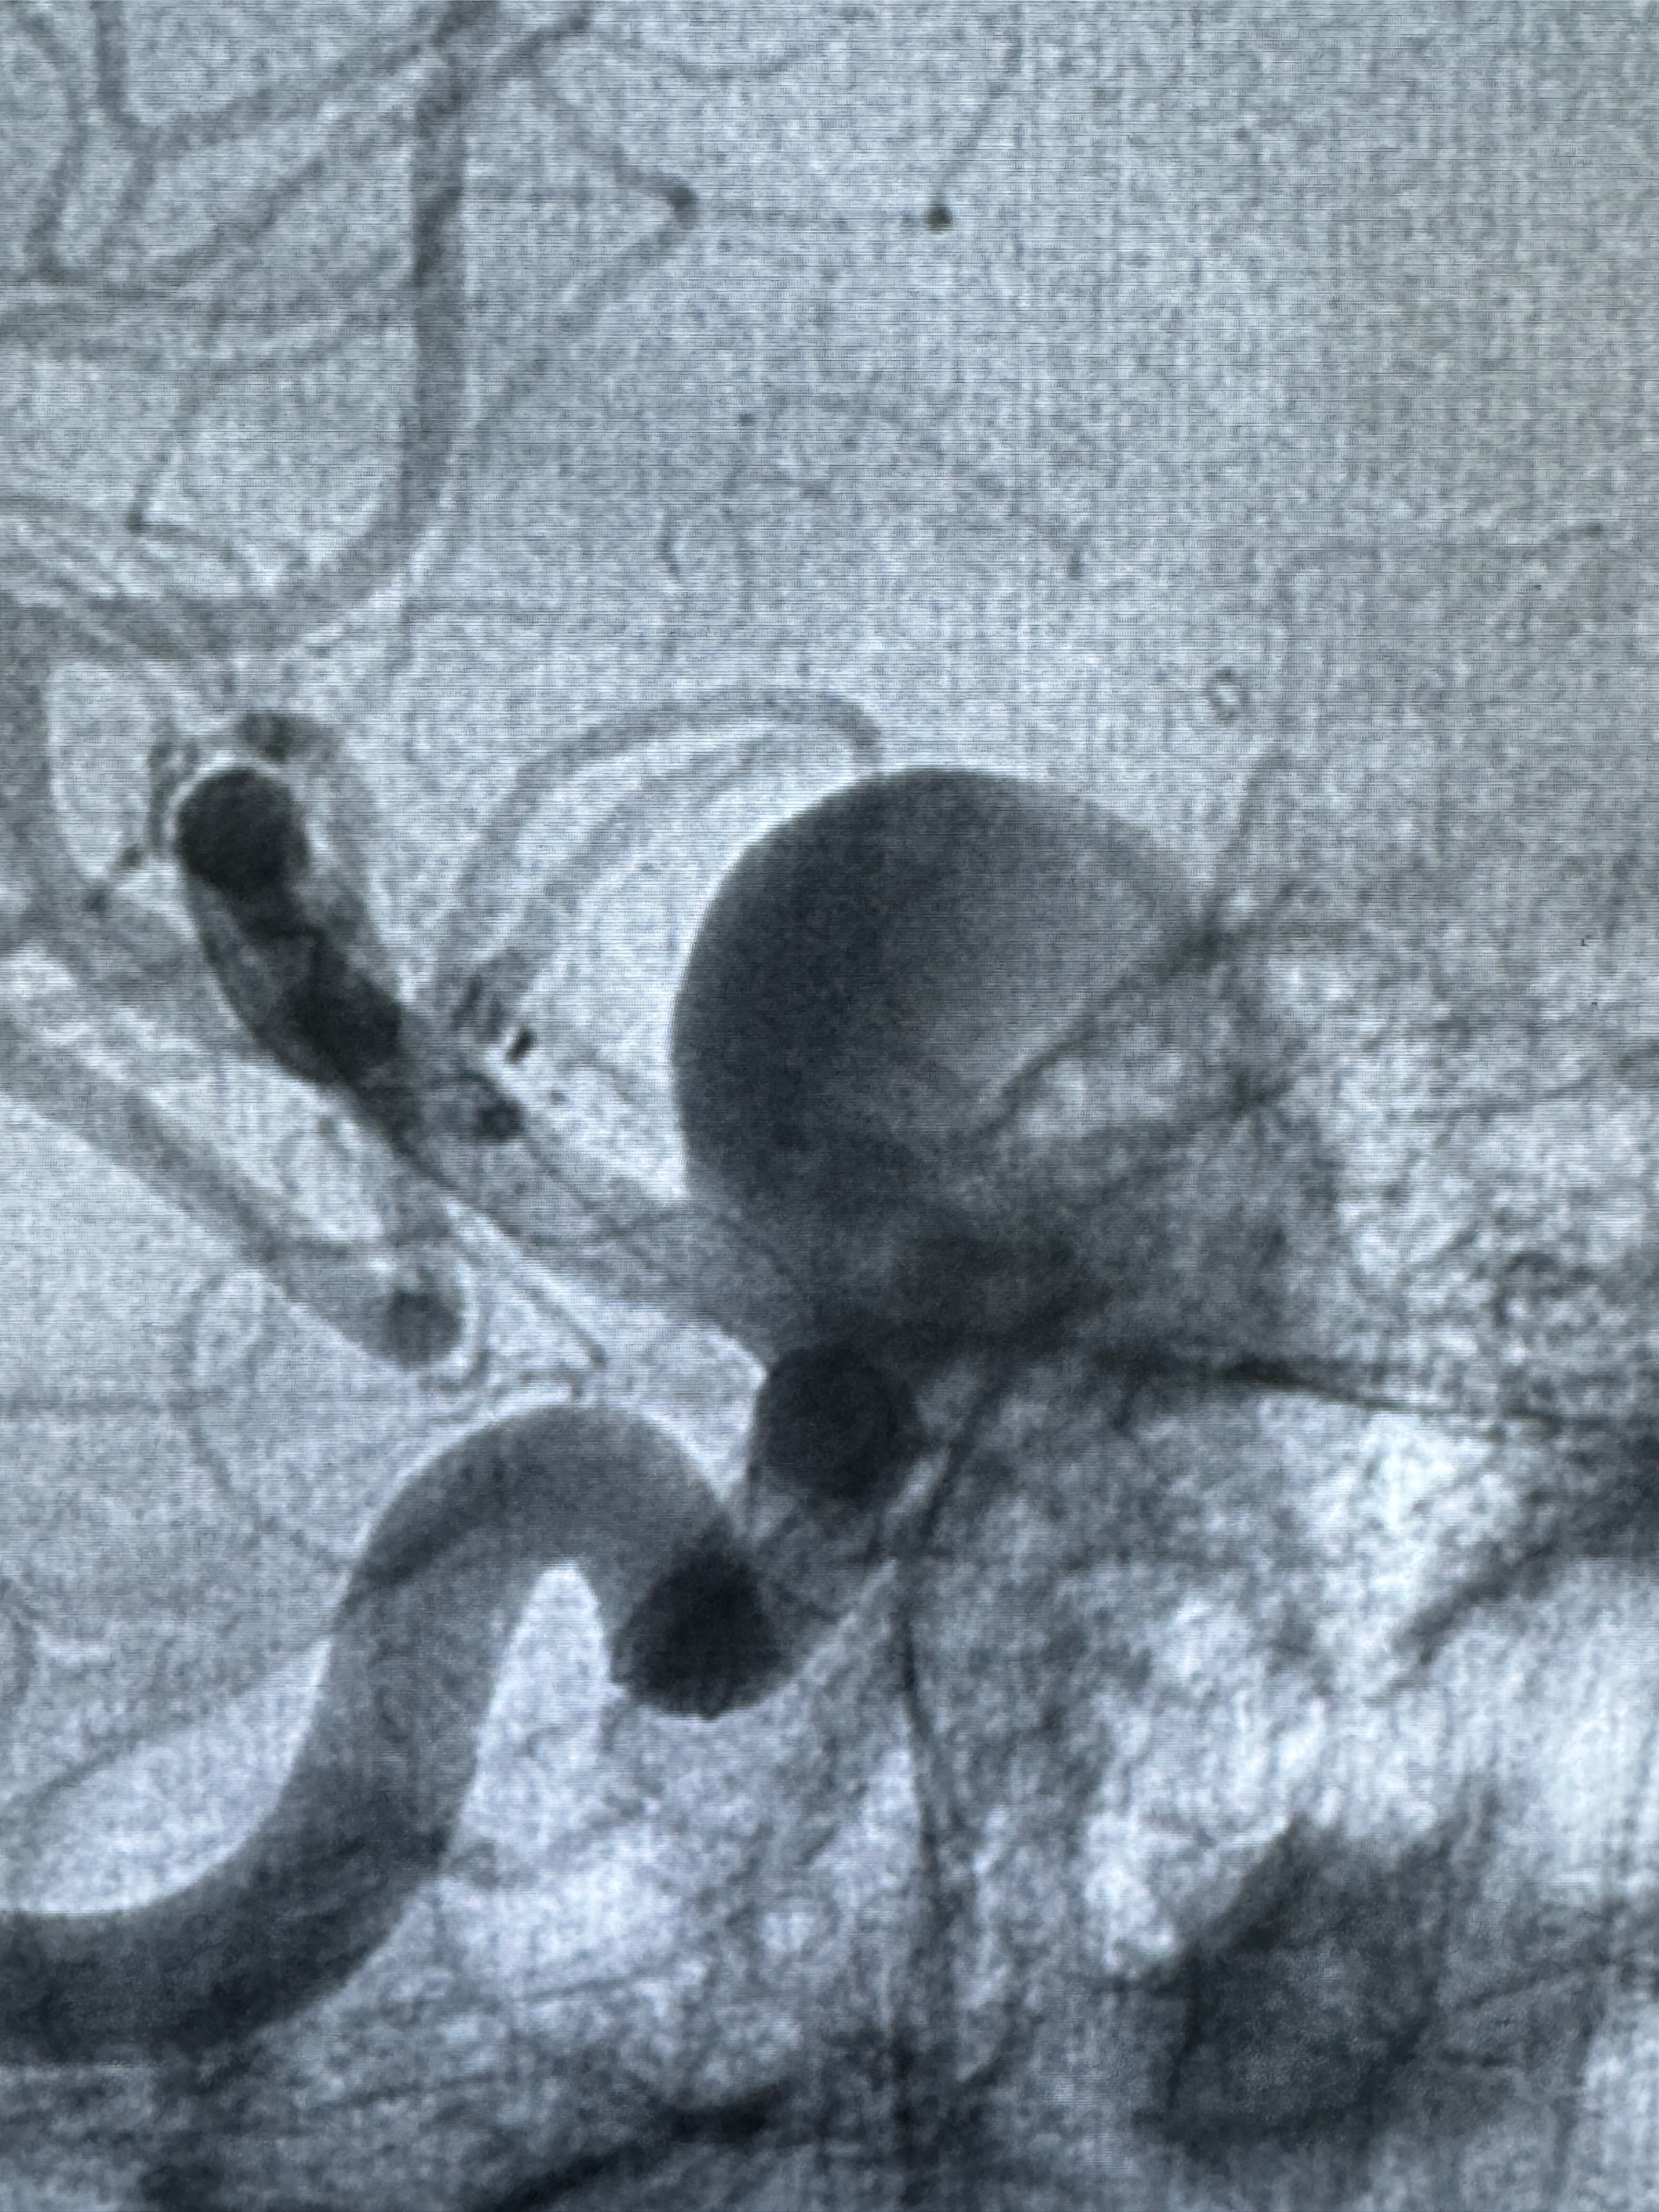

现病史:患者诉2年来反复发作性头痛,顶枕部为主,因自己考虑高血压可能,未予系统检查;患者约20日前无明显诱因下突发剧烈头晕,有天旋地转感,不能睁眼,伴视物模糊;外院查头颅MRI+MRA提示:左侧颈内动脉C6段动脉瘤;遂至复旦大学附属华山医院就诊,于2023-12-08行全脑血管造影提示:右侧颈内动脉C6段动脉瘤,瘤颈6.68mm,动脉瘤大小13.28*12.34mm,建议行密网支架辅助栓塞术治疗,因缺乏相关材料遂出院。现患者仍有顶枕部头痛不适,为求进一步诊疗脑血管病变至我科就诊,收治入院。

2023-12-08 复旦大学附属华山医院 全脑血管造影:右侧颈内动脉C6段动脉瘤,瘤颈6.68mm,动脉瘤大小13.28*12.34mm

2023-12-08外院DSA:右侧颈眼动脉瘤,约13*12mm大小,压颈试验显示左右向及后向前代偿可

旋转3D展示动脉瘤局部的血管构筑

测量动脉瘤的大小:16*13.8*7.6mm大小,较原先变大,考虑双抗后瘤内血栓溶解可能

观察动脉瘤腔内的血流动力学情况